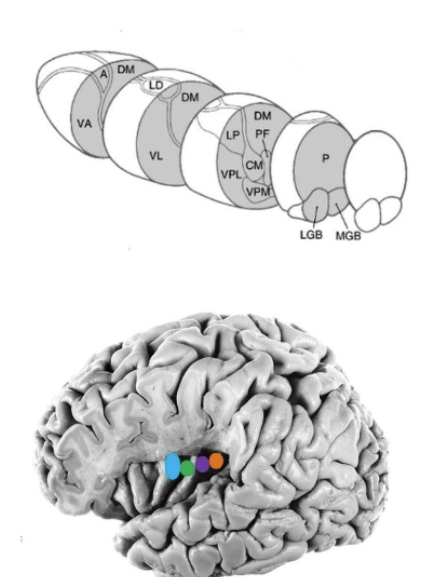

What constitutes the metathalmaus and what is this a continuation of?

Lateral and medial geniculate bodies constitutes the metathalmaus and may be considered as the caudal continuation of the ventral nuclear mass of the thalamus.

Lateral and medial geniculate nucleus

Lateral geniculate nucleus

LGN is a small, rostrolaterally directed projection from the posterior thalamus.

Laminated, receives input from the retina of both eyes via fiber traveling in the optic tract

Projects to the primary visual cortex (V1) found on the banks of the calcarine sulcus on the medial surface of the occipital lobe.

Medial geniculate nucleus

Recieves auditory input from the inferior colliculus through its brachium.

MGN projects to the primary auditory cortex (A1) associated with the transverse temporal gyri of Heschl

Motor relay nuclei

Projections from these nuclei convey info from the cerebellum and the basal nuclei to the motor cortical fields of the frotnla lobe.

Nuclei within this group:

Ventral anterior nucleus (VA) - Basal Nuclei

Ventral lateral nucleus (VL) - Cerebellum

Ventral anterior nucleus (VA)

Receives afferent from the output structures of the basal nuclei, the internal segment of the globus pallidus and the pars reticulata of the substantia nigra.

SNrp targets —> more medial magnocelluar part of VA

Parvocellular —> input via GPi

VA sends projections to the frontal eye fields (BA8) and the prefrontal cortex

Contributes to loop circuits of basal nuclei system (Oculomotor, motor, associative)

Involved in motor planning and behavior

Ventral lateral nucleus (VL)

Input from both basal nuclei and. cerebellum

Rostral part of VL (VLo or VLa) receives input from the GPi and projects to premotor cortices (including SMA)

Contributes to motor loop circuit of basal nuclei (motor planning)

Caudal portion (VLp) receives input from the deep nuclei of the cerebellum and projects to motor cortex

Contributes to cerebellar circuits for modulating motor activities (limb movements)

Sensory relay nuclei

Ventral posterior complex (VP)

Ventral posteriorlateral nucleus (VPL)

Ventral posteriormedial nucleus (VPM)

Ventral posterior inferior nucleus (VPI)

Contents

Ventral posteriorlateral nucleus (VPL), site of termination of somatosensory pathways representing body

Ventral posteriormedial nucleus (VPM), where trigeminal representing face and oral cavity terminate.

Ventral posterior inferior nucleus (VPI) in a small ares between VPL and VLM

VPI to oral part of VPL receives vestibular info and project to the posterior insular vestibular cortex (PIVC) @ the posterior ends of the inusla and vestibular cortex of the pariteal lobe (in depths of central sulcus(3a) and rostral tip of the intrapariteal sulcus (2v).

VP projects to the primary somatosensory cortex (S1) associated with the postcentral gyrus and posterior paracentral gyrus of the pariteal lobe.